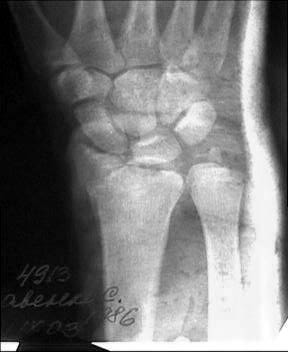

Больной из соседнего района 17 лет получил травму 8 09 03. Перелом по классификации E.Muller -В2

Неполный внутрисуставной перелом лучевой, тыльного края (Barton) Наложена гипсовая повязка рис 08 09. Через месяц на контрольной рентгенограмме найдено вывих л\з сустава. Рентгенограмма при обращении в нашу больницу 21 10 03 рис 21 10. На данные момент имеется умеренно выраженная контрактура, умеренные нейровегетативные нарушения.Обдумываем несколько вариантов лечения:1) Продолжить консервативное лечение и провести артродез, если останется болевой синдром.2) Провести открытую репозицию, устранить вывих, фиксировать отломок пластиной по тыльной поверхности.3) Провести артродез в лучезапястном суставе

Прооперировали. Провели откытую репозицию , фиксацию спицами, иммобилизация гипсовой повязкой.